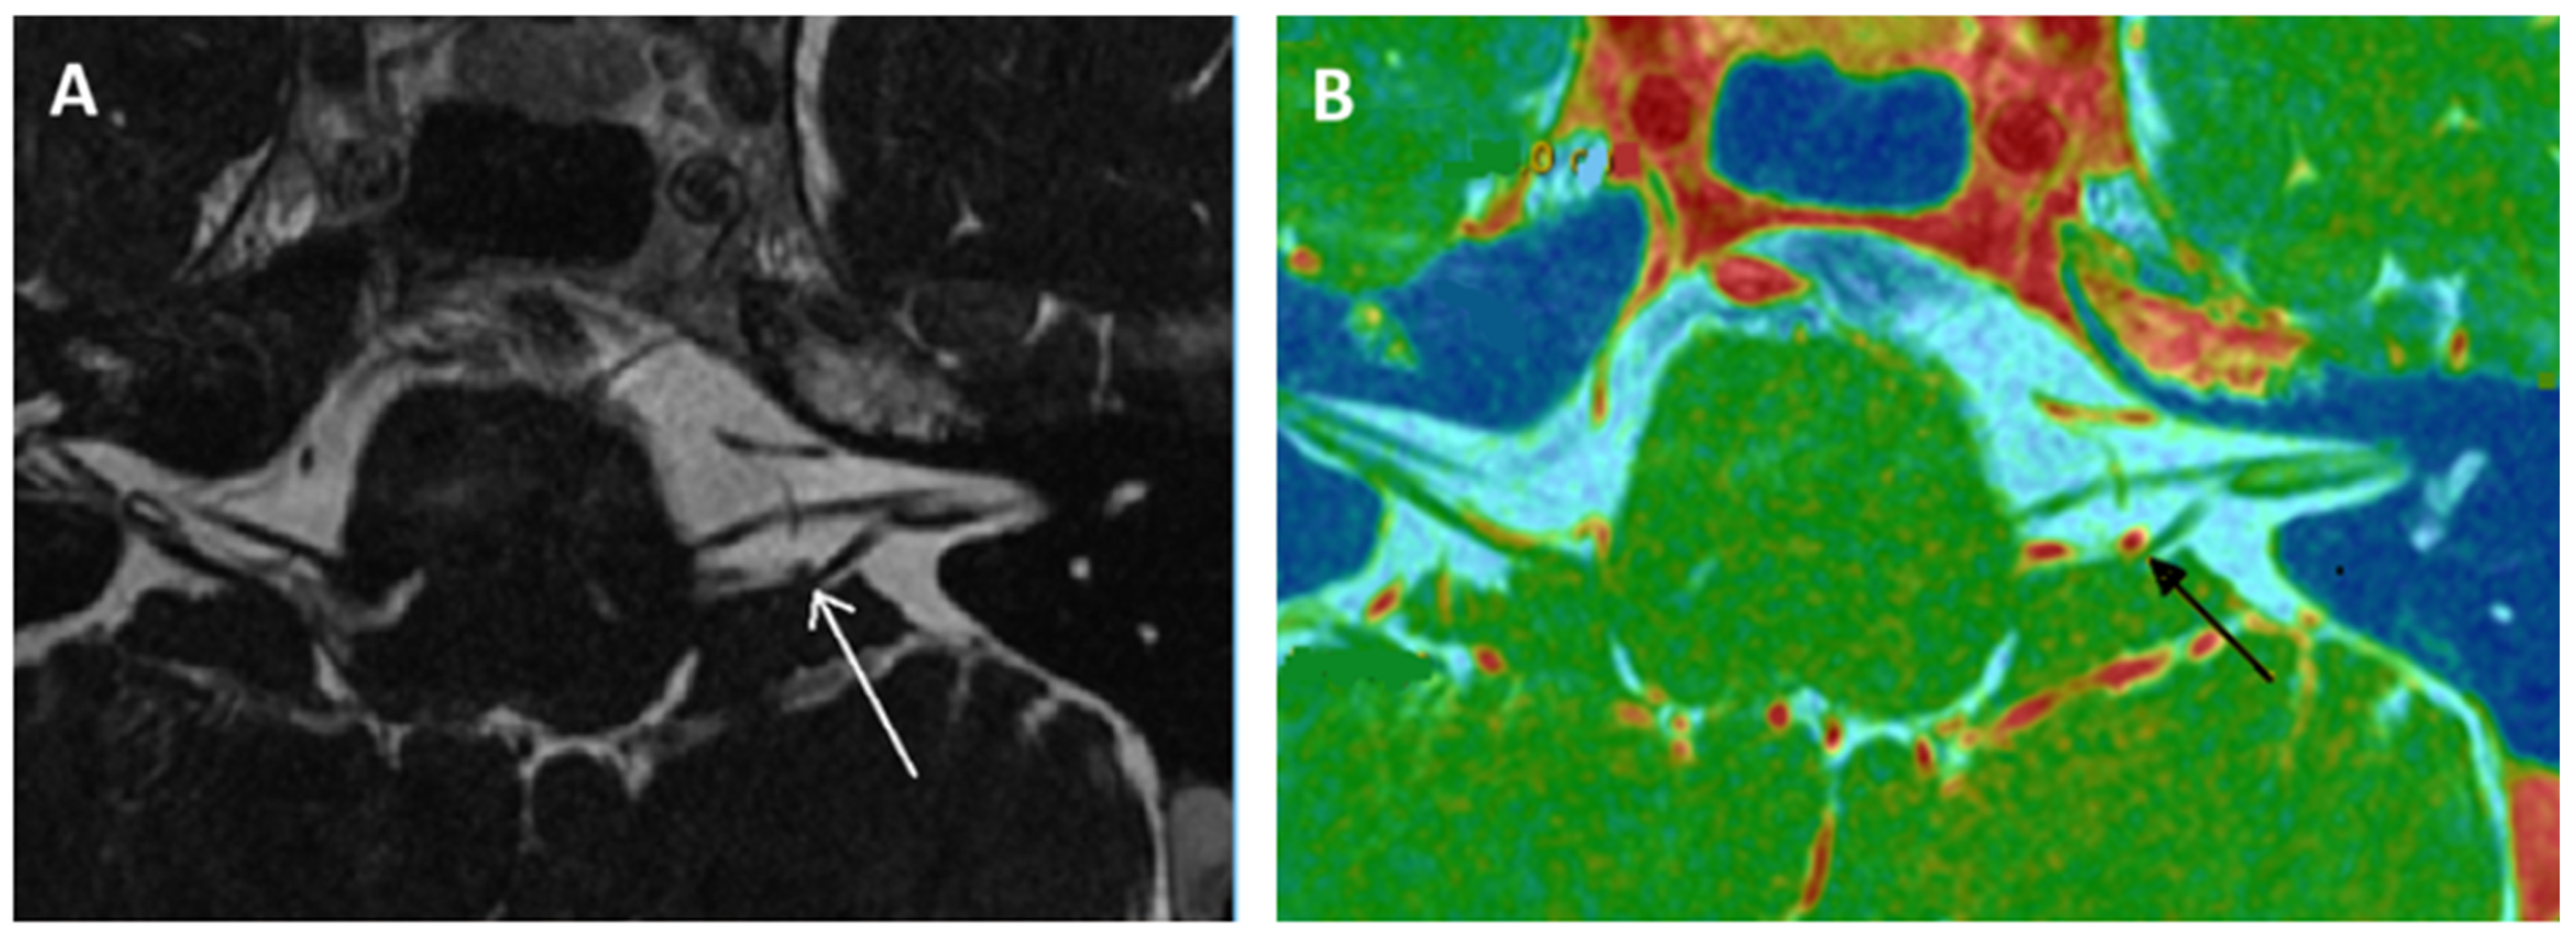

- Kierig, E.; Gerb, J.; Boegle, R.; Ertl-Wagner, B.; Dieterich, M.; Kirsch, V. Vestibular paroxysmia entails vestibular nerve function, microstructure and endolymphatic space changes linked to root-entry zone neurovascular compression. J. Neurol. 2023, 270, 82–100. [Google Scholar] [CrossRef] [PubMed]

- Idriss, S.A.; Thai-Van, H.; Altaisan, R.; Ltaief-Boudrigua, A.; Reynard, P.; Ionescu, E.C. The Narrowed Internal Auditory Canal: A Distinct Etiology of Pediatric Vestibular Paroxysmia. J. Clin. Med. 2022, 11, 4300. [Google Scholar] [CrossRef]

- Ionescu, E.C.; Reynard, P.; Idriss, S.A.; Ltaief-Boudriga, A.; Joly, C.A.; Thai-Van, H. The “Near”-Narrowed Internal Auditory Canal Syndrome in Adults: Clinical Aspects, Audio-Vestibular Findings, and Radiological Criteria for Diagnosis. J. Clin. Med. 2023, 12, 7580. [Google Scholar] [CrossRef]